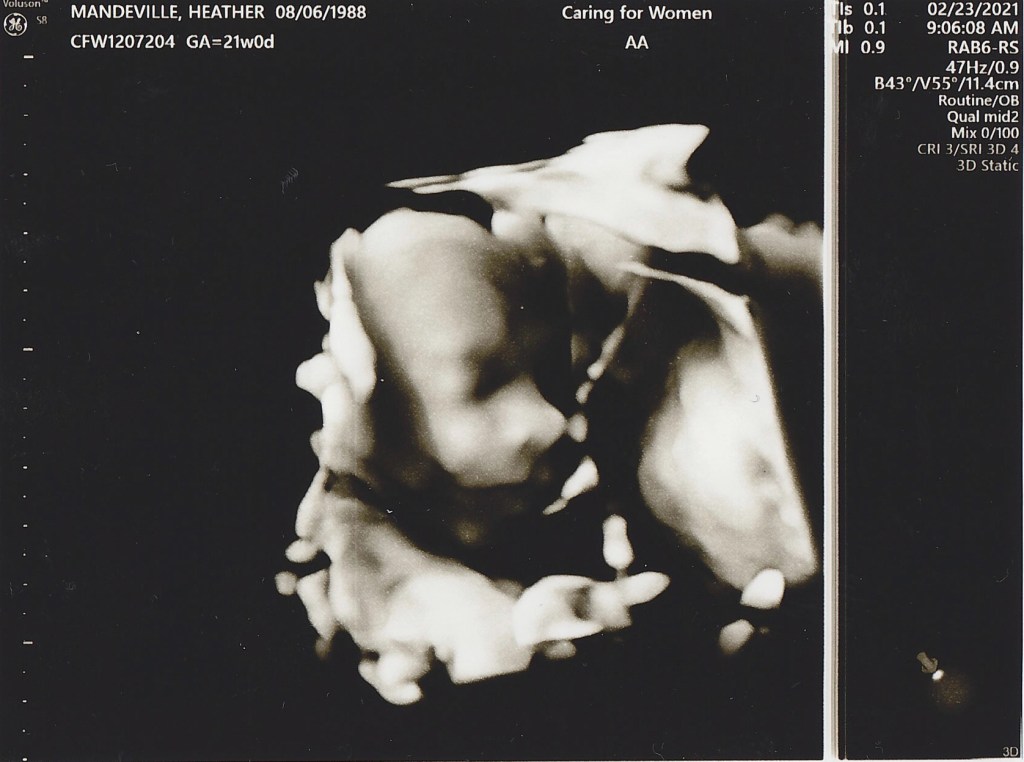

20 week sonogram

IT’S A BOY!! We found out today we are having a boy and we could not be more excited! Everything is looking good, Heather and the baby are healthy and he is progressing as expected. Now we get to start really planning to welcome him into this world, so many things to do in the next 20 weeks!